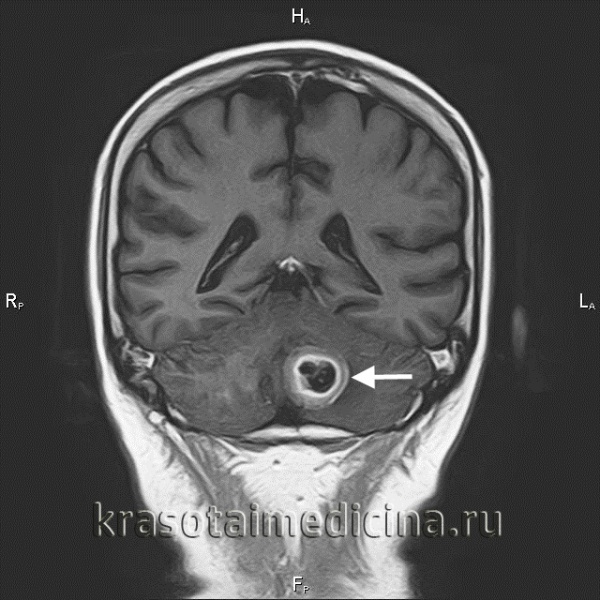

Метастатические опухоли мозга

Метастатические опухоли мозга – вторичные очаги, возникающие вследствие местного агрессивного роста, гематогенного и лимфогенного метастазирования злокачественных новообразований других локализаций. У 30% больных протекают бессимптомно. В остальных случаях опухоли головного мозга проявляются головными болями, головокружениями, тошнотой, рвотой, очаговой симптоматикой, психическими и эмоциональными нарушениями. При поражении спинного мозга возникают боли, чувствительные и двигательные расстройства. Диагноз выставляется с учетом анамнеза, симптомов, КТ, МРТ и других исследований. Лечение – радиотерапия, реже оперативное удаление или химиотерапия.

Метастатические опухоли мозга – группа злокачественных новообразований различного происхождения, возникших в спинном либо головном мозге в результате распространения клеток первичной опухоли. Метастазы в головной мозг выявляются у каждого пятого онкологического больного. Метастатическое поражение спинного мозга по различным данным наблюдается у 30-70% пациентов. По данным исследователей, вторичные поражения ЦНС встречаются примерно в 10 раз чаще первичных.

80% метастатических опухолей головного мозга располагаются в зоне больших полушарий, 15% – в мозжечке, 5% - в стволе мозга. Большинство вторичных очагов в спинном мозге локализуются на уровне нижних грудных либо верхних поясничных позвонков. Поражения твердой мозговой оболочки составляют около 10% от общего количества метастатических опухолей мозга. Более 70% метастазов множественные, что ухудшает прогноз. Гистологическое строение вторичной опухоли – как у первичного новообразования. Симптомы обусловлены как непосредственным давлением узла на нервные структуры, так и перифокальным отеком окружающих тканей.

Настораживающими признаками в отношении новообразований головного мозга являются головные боли, тошнота, эпилептиформные припадки (обнаруживаются у 35% пациентов) и прогрессирующая очаговая симптоматика. Подозрение на вторичный процесс в спинном мозге возникает при продолжительных нарастающих болях, двигательных и чувствительных нарушениях и расстройствах деятельности тазовых органов. Основные инструментальные методы диагностики метастатических опухолей мозга – КТ и МРТ. Обычно исследования начинают с более доступной КТ головного мозга и КТ позвоночника, а полную информацию о количестве, размере и расположении очагов получают при проведении МРТ с контрастным усилением. При поражении спинного мозга также информативна люмбальная пункция с ликвородинамическими пробами.